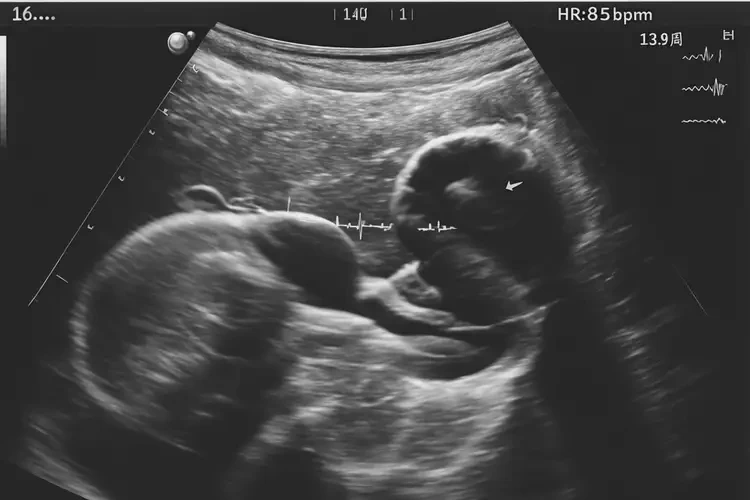

孕14周1天胎心85有危險嗎

胎心85次/分鐘對孕14周1天的胎兒來說可能偏低。正常情況下,孕14周的胎兒心率應(yīng)在140-170次/分鐘之間。胎心過低可能意味著胎兒存在某些健康問題,需要進(jìn)一步檢查和監(jiān)測。

孕14周1天胎心85有危險嗎(圖1)